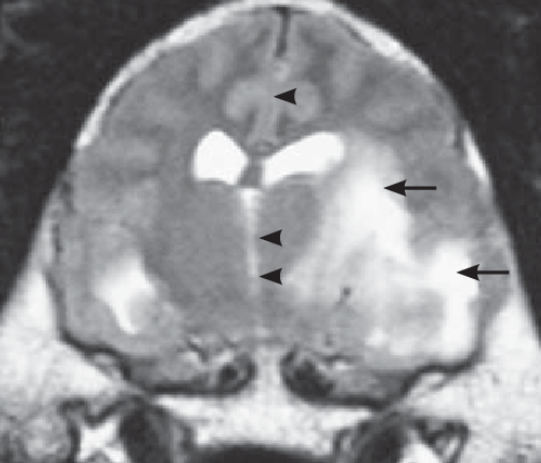

반려견의 MRI 검사에서 midline shift가 관찰될

원인이 무엇이건 뇌병변이 있을 때 일부 개들에서는 위 사진의 화살표 머리처럼 중심이 한쪽으로 밀리는 현상이 자주 관찰된다. 이걸 두고 midline shift라고 하는데 이 현상이 예후에는 어떤 영향을 끼칠까? 에 대한 논문이 나왔다. 상식선에서 생각해 보아도 예후가 불량할 것이라는 추론이 가능하지만 추론과 실제 증명은 의미가 다르니 참고할 근거 자료이다.